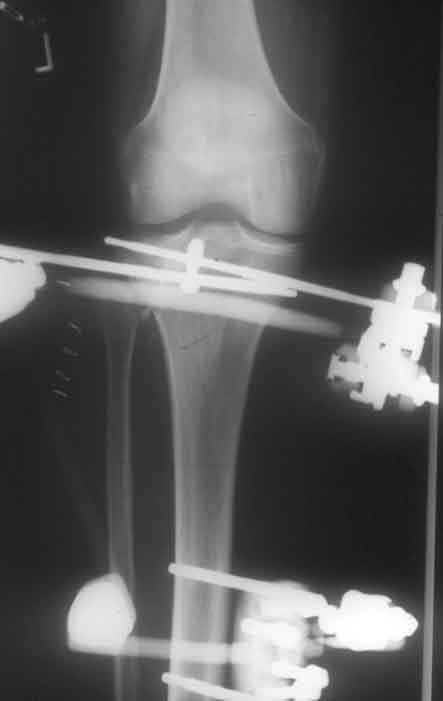

Hoffmann II Montage mit freier Pinplazierung proximal. Wenige Tage nach der Operation besteht freie Beweglichkeit im Kniegelenk Befund 8 Wochen nach der Operation, der Fixateur kann entfernt werden.